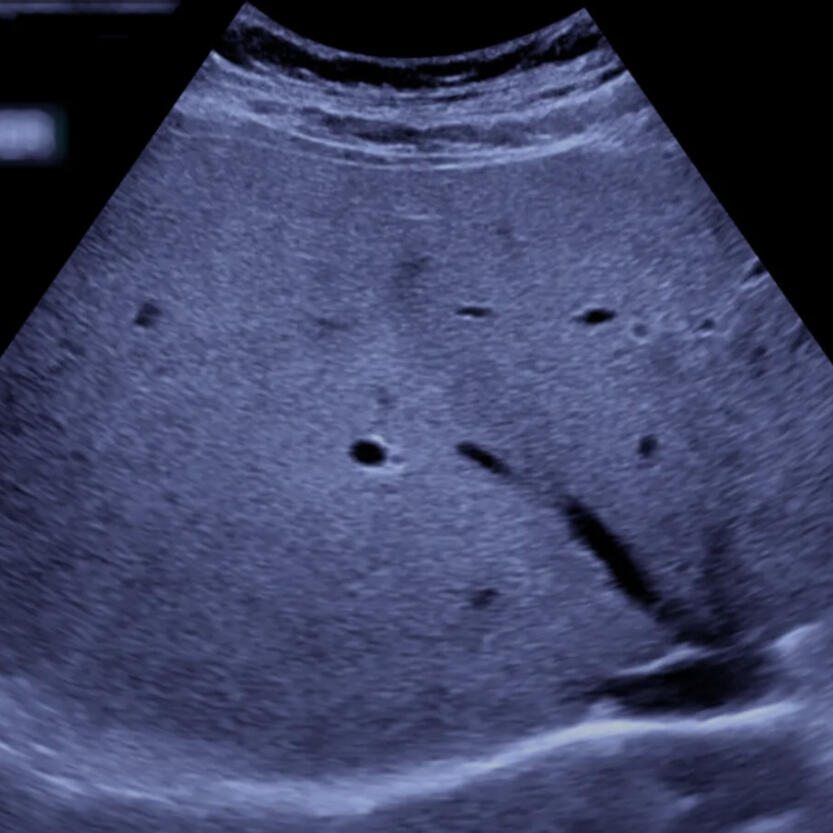

- Profesionalūs echoskopiniai tyrimai (krūtinės ir pilvo organai)

Pilvo ultragarsinis tyrimas